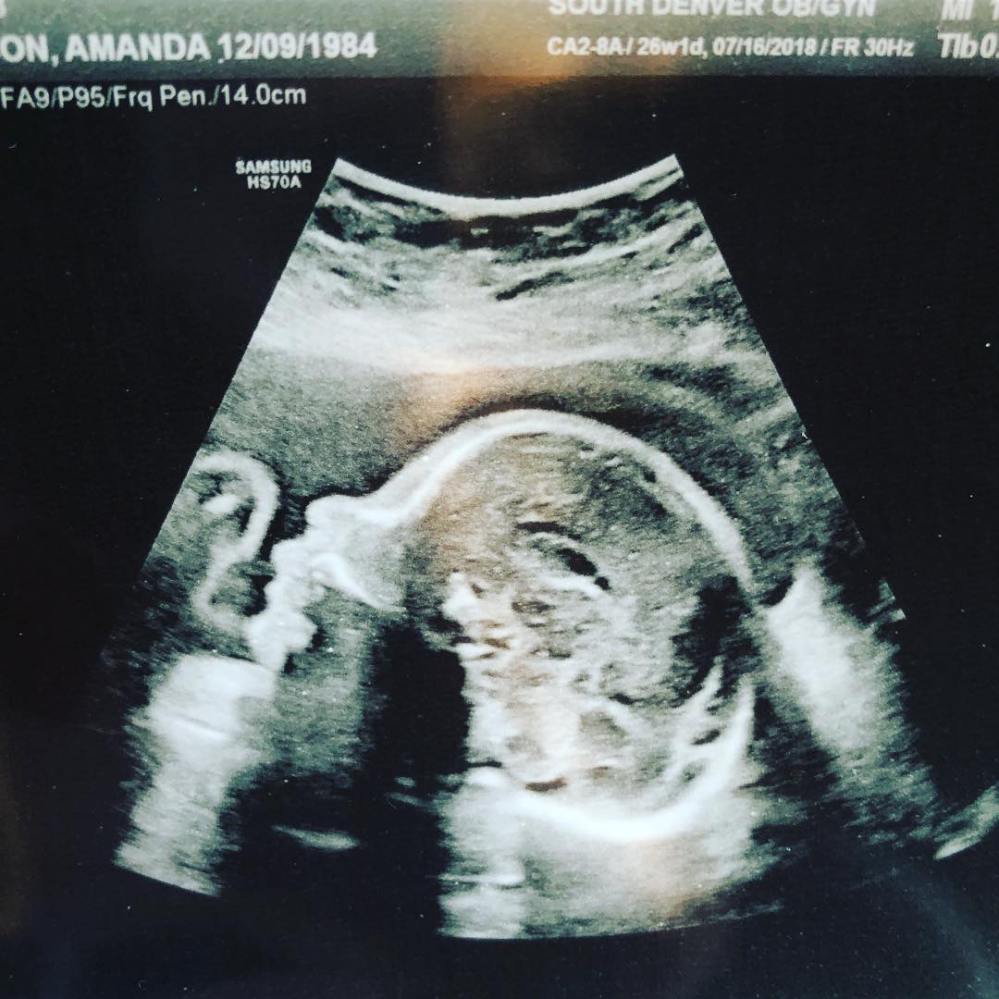

Our 26 week baby appointment confirmed again that Baby Rabon #2 is a girl! We are both well and healthy. I tested negative for gestational diabetes, my blood pressure was perfect, and the ultrasound technician was able to confirm that Baby Girl’s aortic arch looks good. We also got to watch her yawn, which was probably one of the cutest things ever, and Jonathan really enjoyed getting to see his baby sister.